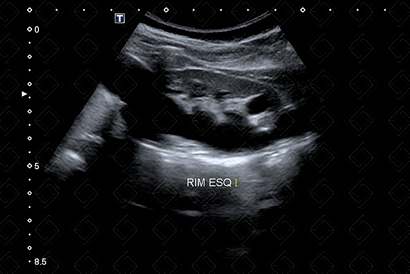

Texto alternativo para a imagem Figura 1. Créditos: Dra. Elazir Mota - Rio de Janeiro/RJ

Descrição da figura 1: Imagem arredondada, anecoica, sem fluxo ao Doppler colorido, na topografia do óstio ureterovesical esquerdo, compatível com ureterocele (seta vermelha).

• Ultrassonografia do aparelho urinário: Imagem arredondada, anecoica, sem fluxo ao Doppler colorido na topografia do óstio ureterovesical acometido, melhor avaliada na fase de enchimento vesical. Atenção! Quando a bexiga estiver muito repleta, a ureterocele pode estar colabada e não ser visualizada (figuras 1, 3 e 4);